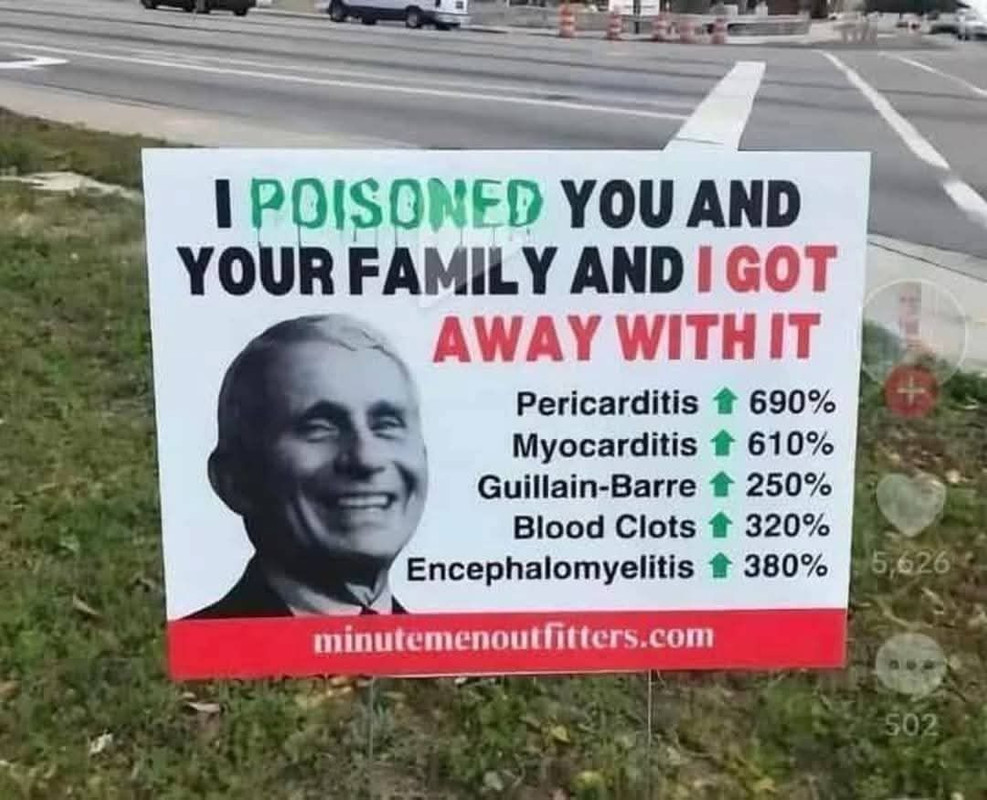

Τα εμβόλια κατά Covid-19 αποδείχθηκε ότι προκαλούν σε αρκετές περιπτώσεις νευρολογικές, αιματολογικές και καρδιακές παθήσεις στη μεγαλύτερη παγκόσμια μελέτη ασφάλειας εμβολίων έως σήμερα.

Τα εμβόλια mRNA που έγιναν από την Pfizer Inc., BioNTech SE και Moderna Inc., κτυπούν την καρδιά, ενώ προκαλούν έναν τύπο θρόμβου αίματος στον εγκέφαλο μετά ανοσοποίηση με εμβόλια ιικού φορέα τα εμβόλια της AstraZeneca Plc.

Τα εμβόλια ιικού φορέα συνδέονται με το σύνδρομο Guillain-Barre, μια νευρολογική διαταραχή στην οποία το ανοσοποιητικό σύστημα επιτίθεται κατά λάθος στο περιφερικό νευρικό σύστημα.

Περισσότερες από 13,5 δισεκατομμύρια δόσεις εμβολίων Covid έχουν χορηγηθεί παγκοσμίως τα τελευταία τρία χρόνια, όπως αποκάλυψε το Global Vaccine Data Network, σε έρευνα 99 εκατομμυρίων εμβολιασμένων ατόμων σε οκτώ χώρες, με στόχο τον εντοπισμό υψηλότερων του αναμενομένου κρουσμάτων μετά από εμβολιασμό για τον Covid, σε πολλές περιπτώσεις αυτά ήταν φονικά.

Η μυοκαρδίτιδα, ή φλεγμονή του καρδιακού μυός, εντοπίστηκε σταθερά μετά από μια πρώτη, δεύτερη και τρίτη δόση εμβολίων mRNA, σύμφωνα με τη μελέτη.

Η υψηλότερη αύξηση στην αναλογία παρατηρούμενου προς το αναμενόμενο παρατηρήθηκε μετά από δεύτερη δόση με το Moderna.

Η πρώτη και η τέταρτη δόση του ίδιου εμβολίου συνδέθηκαν επίσης με αύξηση κινδύνου της περικαρδίτιδας.

Οι ερευνητές βρήκαν μια στατιστικά σημαντική αύξηση των περιπτώσεων του συνδρόμου Guillain-Barre εντός 42 ημερών από μια αρχική δόση του εμβολίου ChAdOx1 ή «Vaxzevria» που αναπτύχθηκε στην Οξφόρδη – κάτι που δεν παρατηρήθηκε με εμβόλια mRNA.

Το ChAdOx1 συνδέθηκε με τριπλάσια αύξηση της θρόμβωσης του εγκεφαλικού φλεβικού κόλπου, ενός τύπου θρόμβου αίματος στον εγκέφαλο, που εντοπίστηκε σε 69 συμβάντα, ενώ θα ανέμενε κανείς μόνο 21.

Η μυοκαρδίτιδα συνδέθηκε επίσης με μια τρίτη δόση ChAdOx1 σε ορισμένους, αλλά όχι όλους, πληθυσμούς που μελετήθηκαν.

Παρατηρήθηκαν περιπτώσεις οξείας διάχυτης εγκεφαλομυελίτιδας μετά από εμβολιασμό με το εμβόλιο Pfizer-BioNTech.